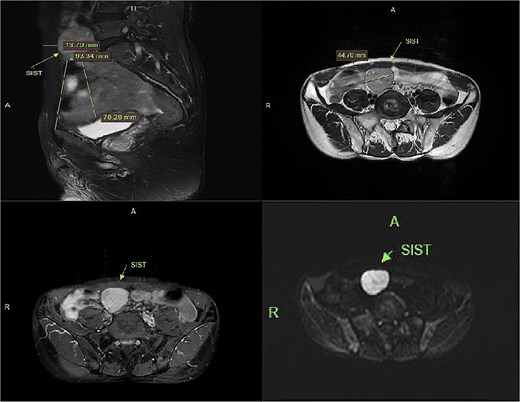

The patient underwent laparoscopic resection under general anesthesia in the lithotomy position. Intraoperative exploration identified a 4 cm ileal mass with significant omental adhesions, which were dissected using an ultrasonic scalpel. En bloc resection of the mass with adjacent ileal segment was performed. Histopathological examination confirmed a poorly differentiated GIST (Fig. 4).

Gross specimen photograph of the laparoscopically resected tumor (right panel) with corresponding histopathological sections (left panel).

Histopathological analysis remains the diagnostic gold standard for GIST. In this case, microscopic examination revealed spindle cell morphology. Immunohistochemical staining was positive for CD117 and DOG1, with a Ki-67 proliferation index of 3%. Findings were negative for SMA, Desmin, and S-100, confirming the diagnosis of GIST [4].